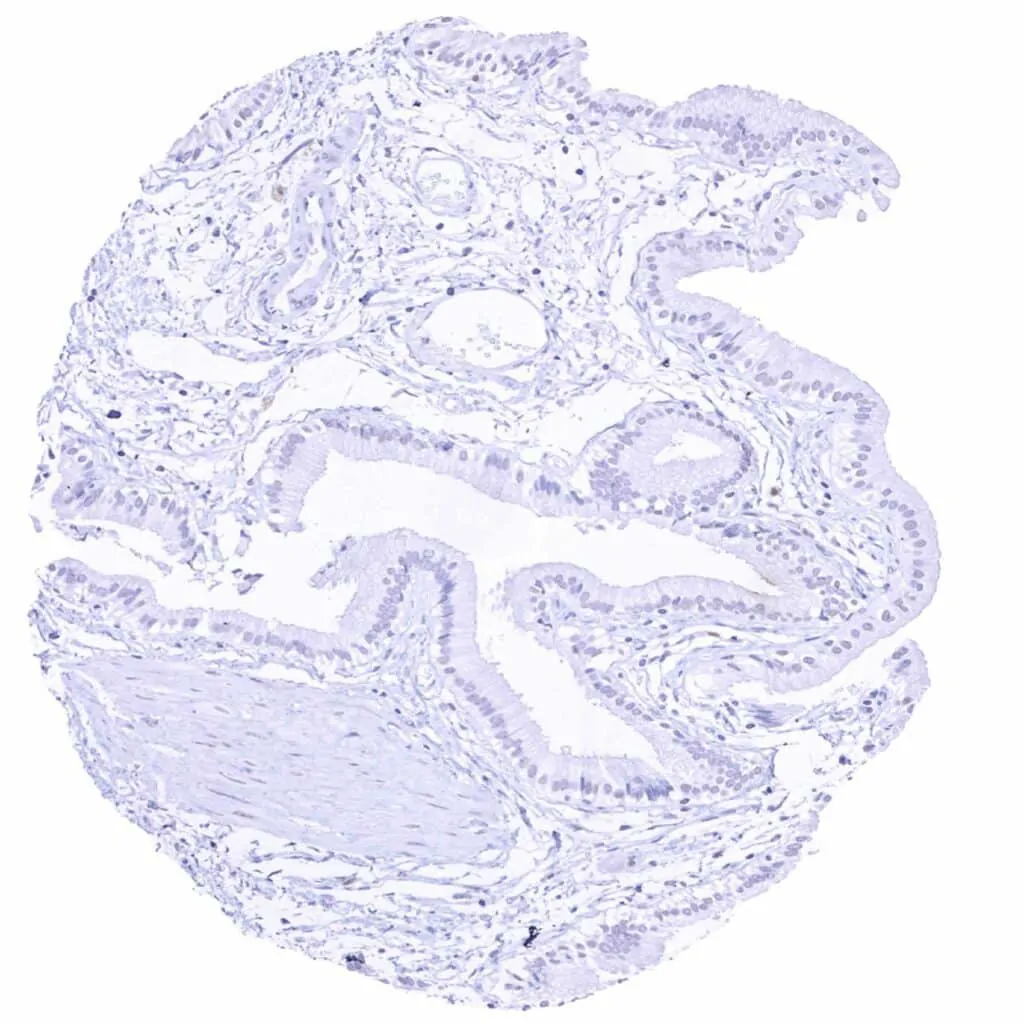

Uterus, endocervix